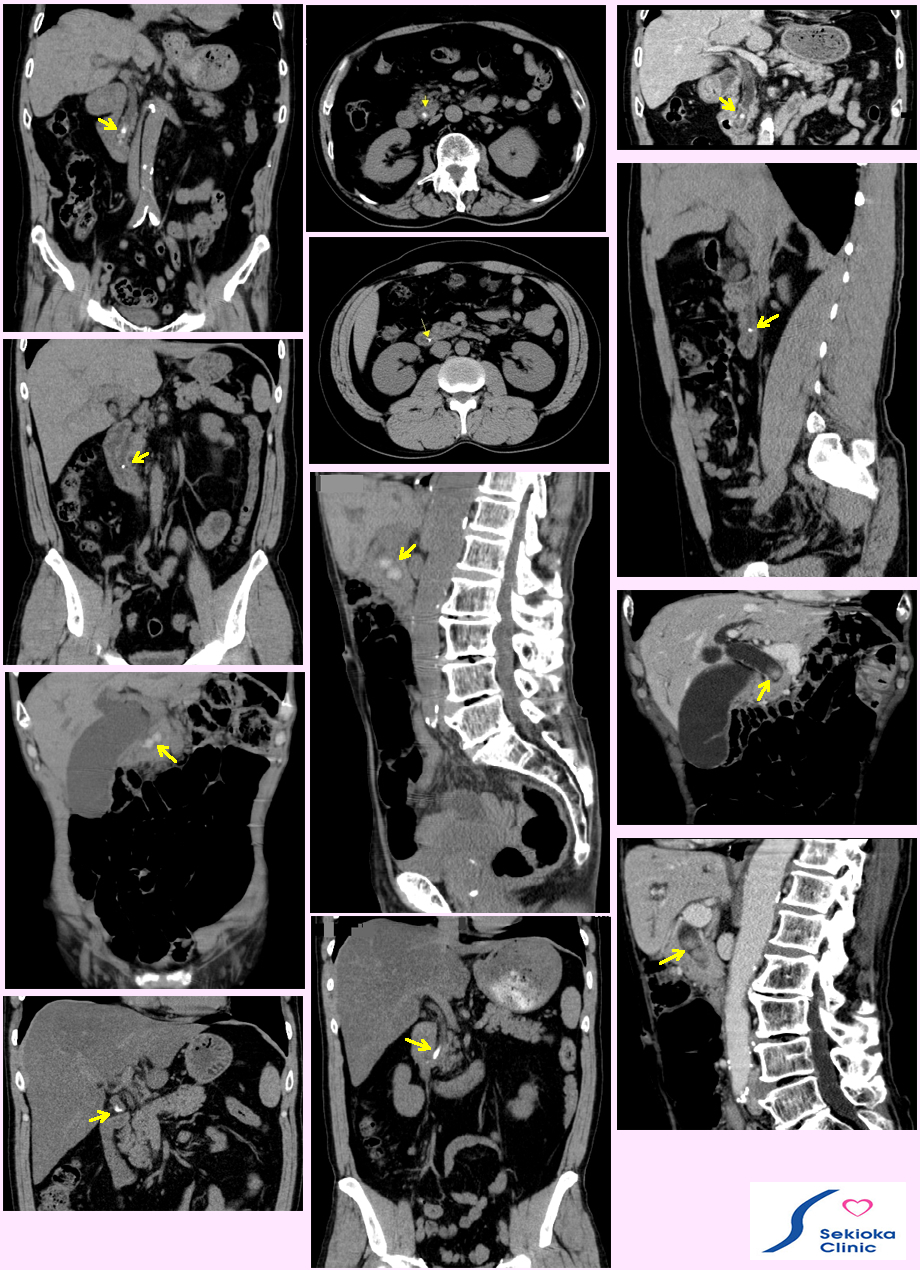

| 診断 | 腹部の圧痛、超音波エコー、CT。血液検査で胆管系、肝障害を示す酵素の上昇を認めることもあります。超音波エコー検査では総胆管に結石がある場合、前方にある腸管の空気で十分診断できないことも多い。CTはMDCTが従来のCTより、任意断面のが観察でき、精細(分機能が高く)で診断に有利です。下段の参考画像はMDCTの画像で適当な断面を複数用いて診断しています。時に造影剤を用いるとがんの合併などより詳細に観察できます。 |